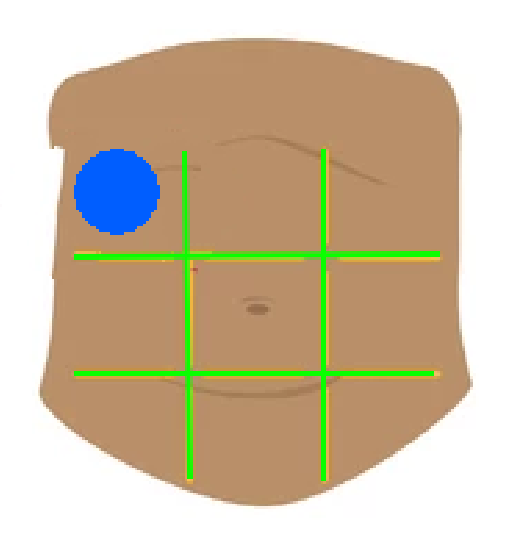

Right hypochondriac region

Left hypochondriac region

Epigastric region

Right lumbar region

Left lumbar region

Umbilical region

Right inguinal region

Left inguinal region

Hypogastric regions